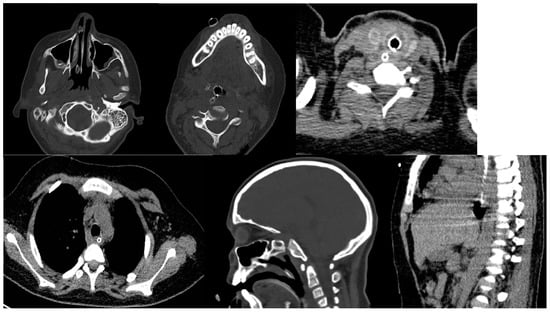

On 34th day in the ICU, general condition of the patient stabilized and slowly improved, confirmed by the improvement of the clinical laboratory test results. Final CT scan of the head, neck and thoracic cavity excluded any other pathologies. (Figure 5). Extubation and tracheostomy tube was removed, and the patient had adequate spontaneous breathing.

Figure 5. Final CT scan showing healing of the head, neck and mediastinum, with no further pathologies.